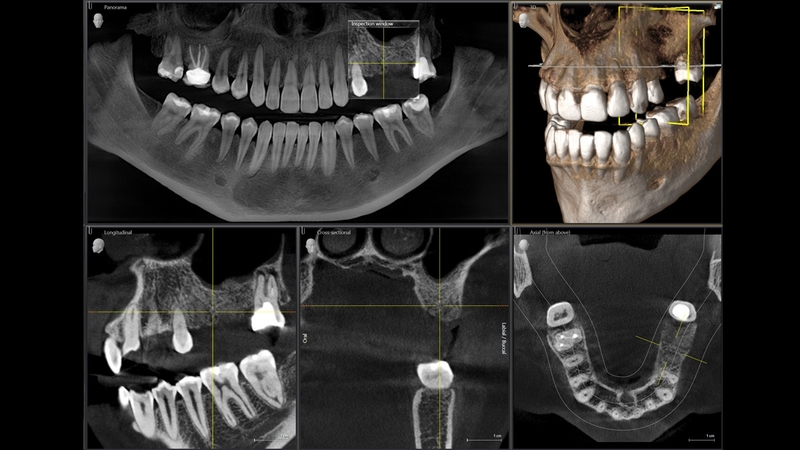

С каждым днем мы стараемся для вас и вашего здоровья - мы стремимся улучшить качество наших услуг! Поэтому спешим сообщить вам, что с 1 июля 2019 года в нашей поликлинике уже функционирует 3D - рентгенодиагностика нового поколения ORTHOPHOS SL 3D от Sironа (Германия). Это - самая новая система из успешного семейства 3D- рентгеновских аппаратов, превосходящая все остальные в функциональности ,качестве и дизайне.

В нашей стоматологии вы сможете сделать рентгенодиагностику, удовлетворяющую самым высоким запросам врачей-стоматологов и с высоким качеством панорамных изображений. 3D-режим позволяет получить объемную съемку зубочелюстной системы даже в сложнейших случаях, интерактивно фокусировать изображение на лингвальном или буккальном слое без дополнительного облучения.